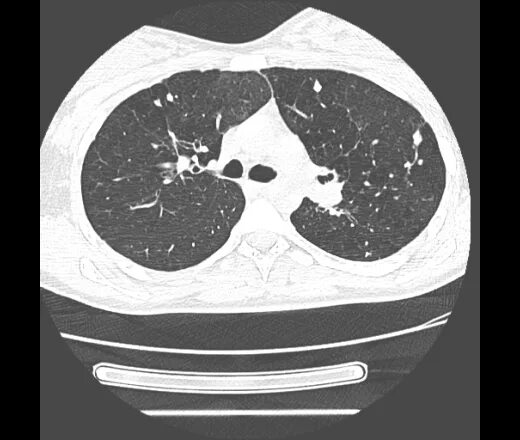

Метатуберкулезные изменения в легких что это означает